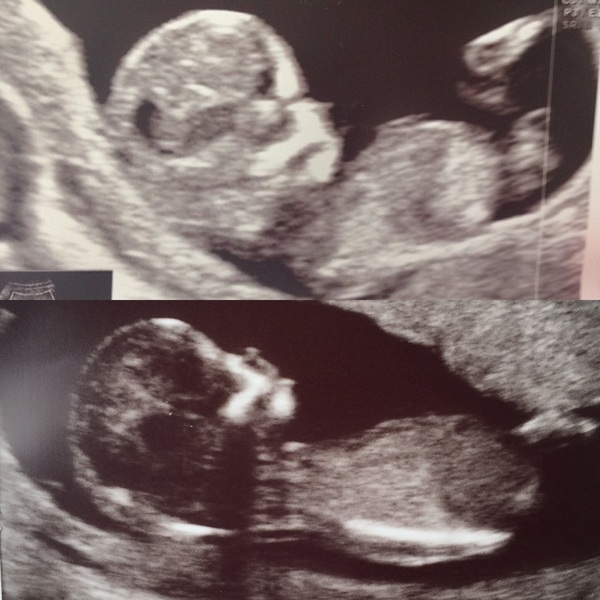

Hi guys don't think I've posted on this thread before! Had my 12 week scan today and I'm 13 weeks exactly. There's a couple of questions I had so hope you don't mind me asking and apologies for the long post! Firstly with my first, a boy, I did the combined test and got a high risk downs result. Had a CVS and thankfully he was all fine. It transpired I had a very low Papp-A (some kind of protein in pregnant women's blood I believe) so even though he was healthy they said he might stop growing at 20 weeks or have growth issues. After that I was scanned regularly but he was fine and born 5 days early weighing 7lb 11. I opted for the combined test again today but worried they'll ring tomorrow to say I'm high risk again - as I was last pregnancy does that mean I'm likely to be high risk this pregnancy?

Secondly, this is more light hearted, I've heard the nub theory/test is good for predicting gender before the second scan. The top pic is my first born who's a boy and the second pic is the scan I had today. What do you reckon? I'm thinking another boy? I'm not bothered either - expecting a boy as no girls in my family for years - but baby being healthy is the most important thing!